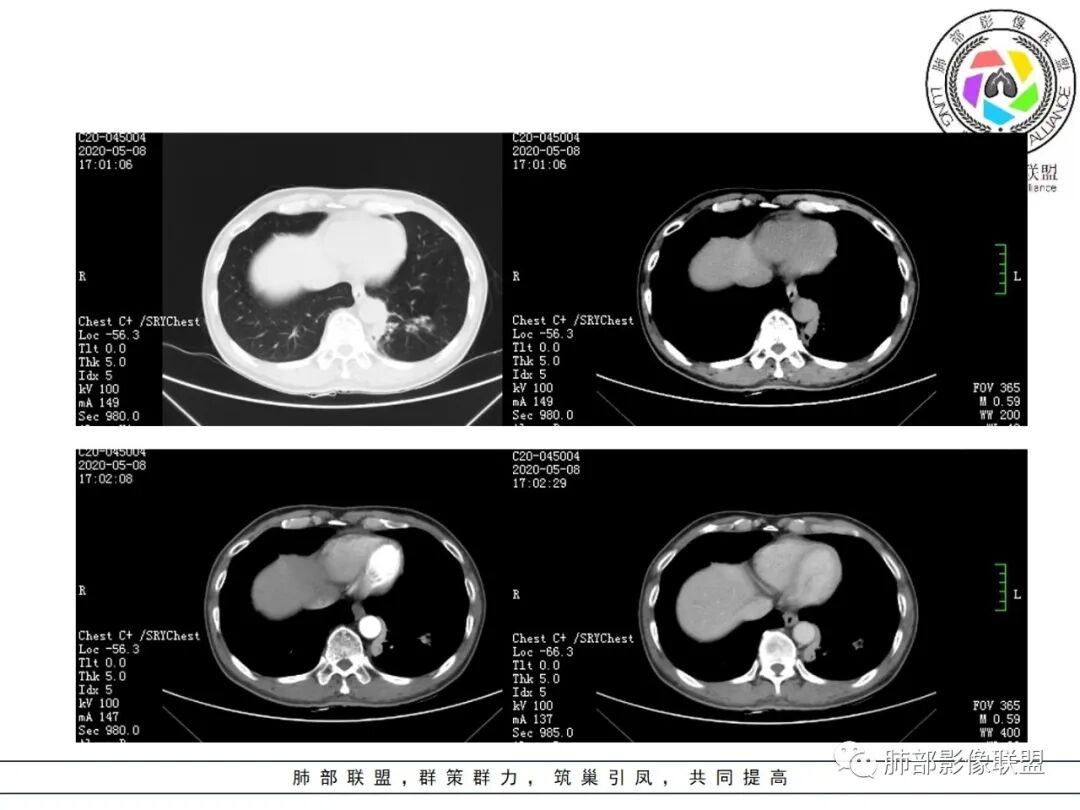

临床资料:老年男性,咳嗽咳痰2月余,慢性病史。有吸烟史40年(现已戒烟),抗感染治疗2周肺部病灶未见吸收。

影像所见:

肺气肿背景。

结节伴分叶。

斑片影,考虑阻塞性炎症。

支气管壁厚,支气管腔内高密度影填充。

周围散在斑片影及结节影,类似“小花花草草”的感觉。